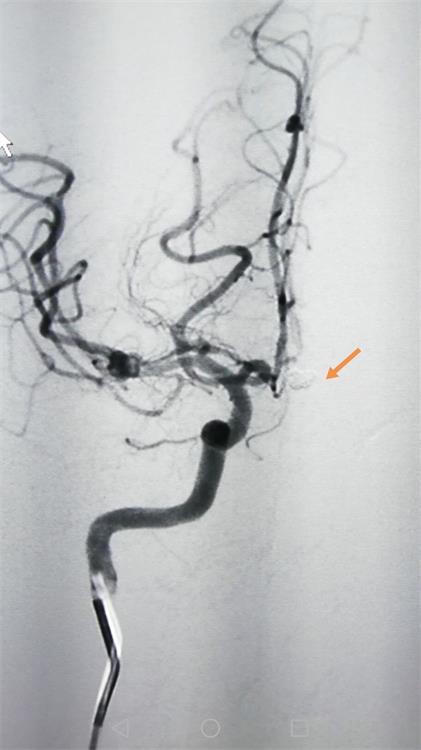

据了解,此名56岁女性患者因突发剧烈头痛入院,经过造影检查显示:左侧前交通动脉瘤(破裂出血责任动脉瘤)合并左侧海绵窦段微小动脉瘤(未破裂),手术方案优先处理出血动脉瘤。

▲栓塞术后动脉瘤完全不显影(黄色箭头所示)